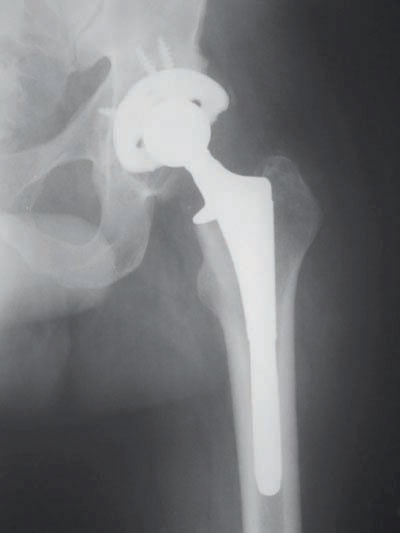

عمليات المفاصل من العمليات الشائعة وأكثرها في مفاصل: الورك, الركبة, الكتف، والكوع, والفائدة الرئيسة للمفصل الصناعي هي تناقص الألم المستمر، ويشعر المريض بأن الطرف أصبح أقوى من قبل، وأن الحركة غير مؤلمة، كما يلاحظ كثير من المرضى تحسناً في حركة المفصل، ففي حالة مفصل الكتف الصناعي يلاحظ المريض أنه يستطيع بعد العمل الجراحي دون مساعدة ويستطيع رفع الأشياء بشكل أفضل.

أما في حالة مفصلي الورك والركبة، فإن المريض يستطيع المشي دون ألم مسافات طويلة، وتصبح حركة المفصل أفضل ودون ألم، وكذلك، فإن شكل الساق يصبح أفضل، حيث يكون قبل العملية مقوسا، ويصبح بعد العمل الجراحي مستقيما، وذا منظر طبيعي. ويمكن تلخيص الأهداف الأساسية لتغير المفصل في ثلاث نقاط «زوال الألم، تحسين وظيفة حركة المفصل، تعديل الاعوجاج».

يتم تحديد عملية استبدال المفصل الصناعي التي تستغرق ساعة ونصف فقط يتم خلالها استبدال المفصل بآخر صناعي دون ألم أو مضاعفات، وقد أجريت أخيرا عملية ناجحة لمريضة تبلغ من العمر 80 عاما، واستطاعت بعدها مزاولة المشي والحركة بكل يسر وبصورة طبيعية.